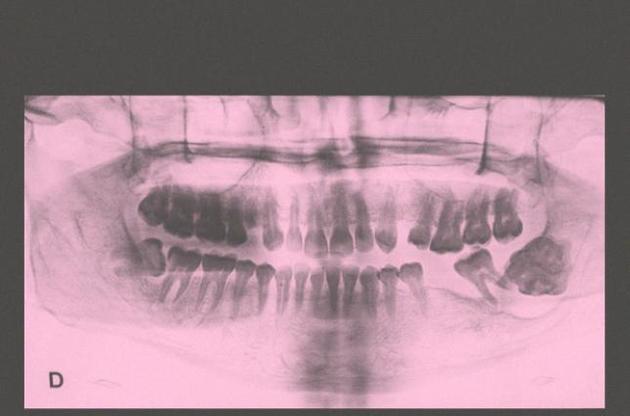

Хлопчик звернувся до лікарів через появу в роті праворуч утворення, схожого на пухлину. Сканування показало наявність безлічі рудиментарних зубів, які містилися у "кишеньці" з тканин. На те, щоб видалити утворення, яке важило 200 грамів, медикам знадобилося п'ять годин. Лікарі також підкреслюють, що хлопчик звернувся за допомогою на ранніх стадіях розвитку захворювання, тому їм вдалося видалити всі зуби.